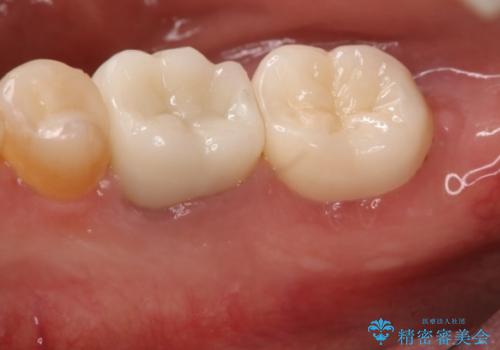

奥歯が痛む オールセラミッククラウン

- 咬んだ時に右下奥歯に痛みがあるとの事で来院された患者様です。

歯の神経は壊死していたため、精密根管治療と補綴治療を計画しました。

セラミックでの治療を希望されたので補綴はオールセラミッククラウンでの治療を選択しました。

痛みは完全に取り除かれ、咬合時の違和感もなく経過は良好です。